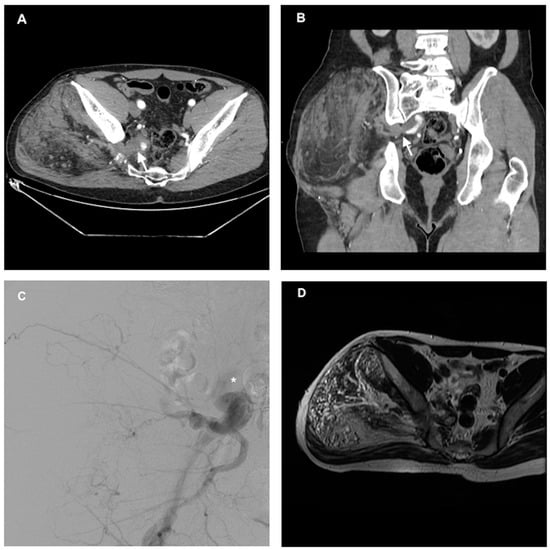

1. Introduction and Clinical Significance

2. Case Presentation

2.2. Treatment and Results